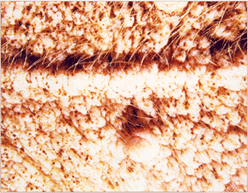

임상증상6

사진53 사진54 사진55

설명53 설명54 설명55